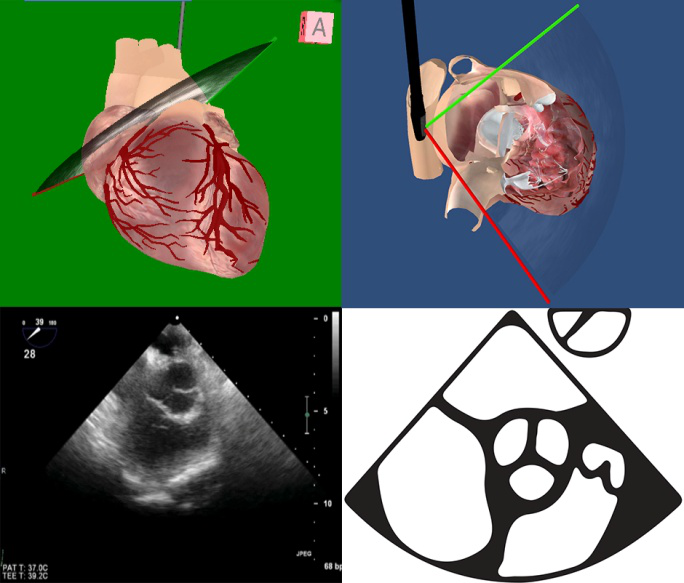

2013年中国麻醉医师术中TEE推广培训协作组提出了适用于麻醉急诊和术中循环监测的TEE-FOCUS的概念,其基本切面有5个,临床实践证明适用于术中循环的监测(图5),本专家共识建议增加升主动脉长轴切面,因为动脉粥样硬化斑块形成的患者数量在增加,此处有无粥样班块及斑块的分级对体外循环手术主动脉插管的安全性监测很重要。

图5 Focus-TEE 6个基本切面的2D图像

图6Tee-Focus中的6个基本切面的模型切面

截至目前,TEE-FOCUS包涵6个基本切面(图5,6),其中有4个关于心脏的基本切面和2个关于大血管的基本切面:①左心室长轴切面,②右心室流入流出道切面,③经胃底心室短轴切面,④食管中段四腔心切面,⑤降主动脉短轴切面,⑥升主动脉长轴切面(新增)。